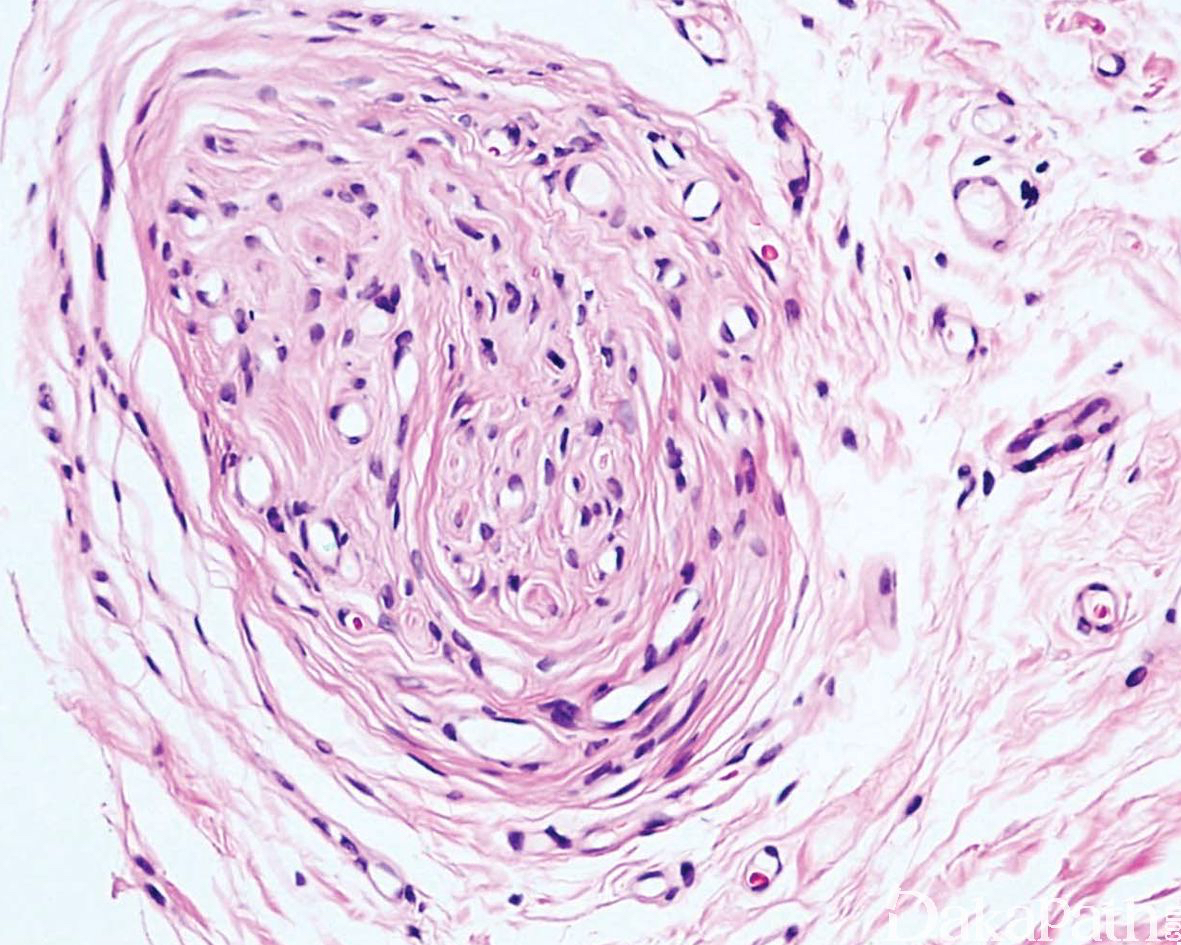

神经束膜细胞呈同心圆状围绕退变的轴突和少量施万细胞,形成特征性的“洋葱头”样结构;

细胞无异型性,罕见核分裂像。